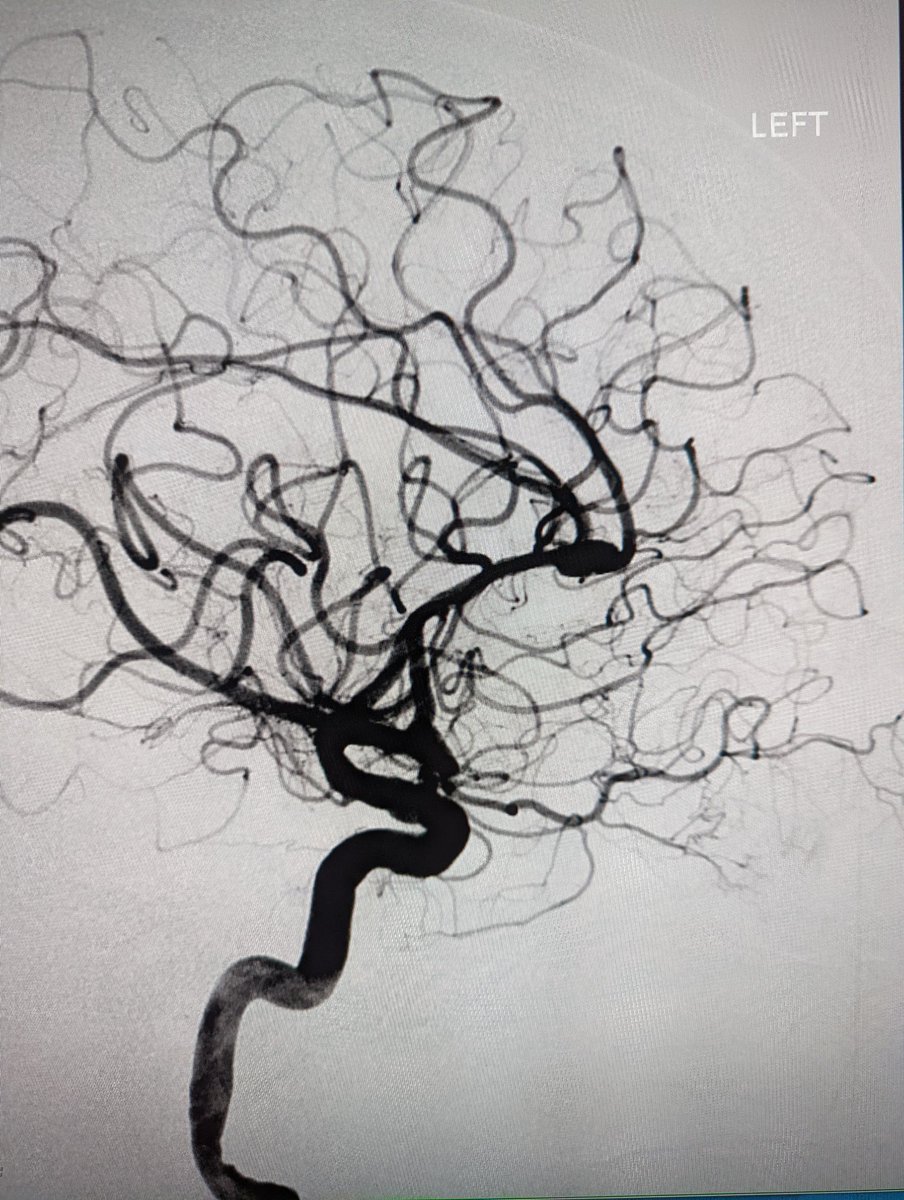

Neuro IR in Minneapolis. Proud product of UCSF. Husband to a Queen, father of 4 princesses. Die hard Buckeyes fan. Work hard, play harderr.